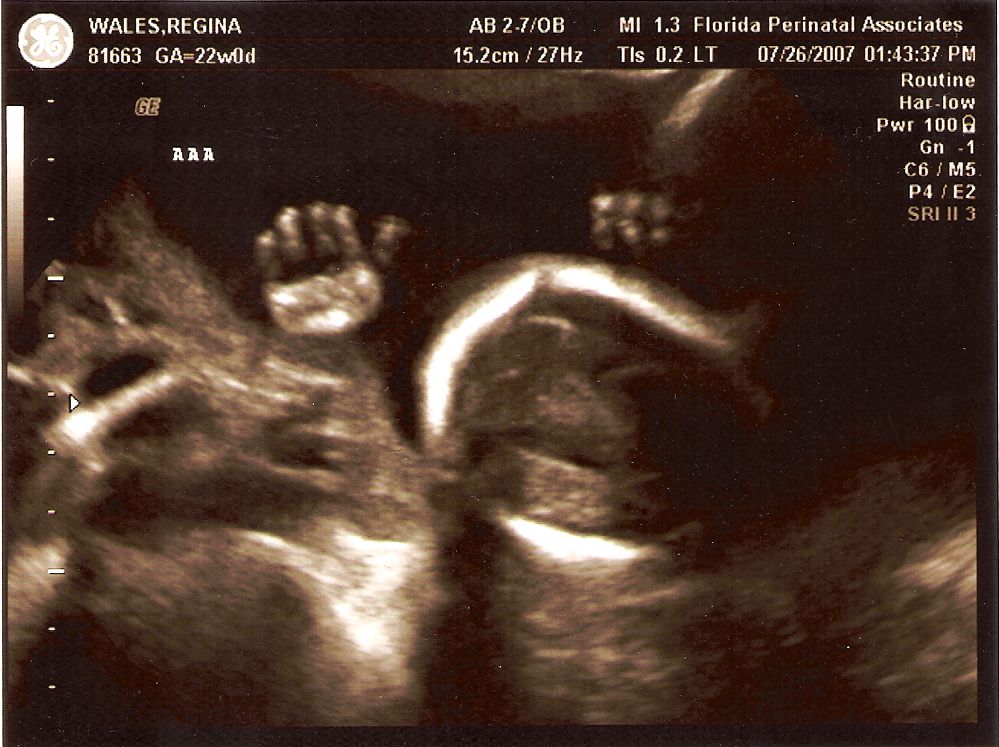

from www.mwales.net

More Ultrasounds of the Twins